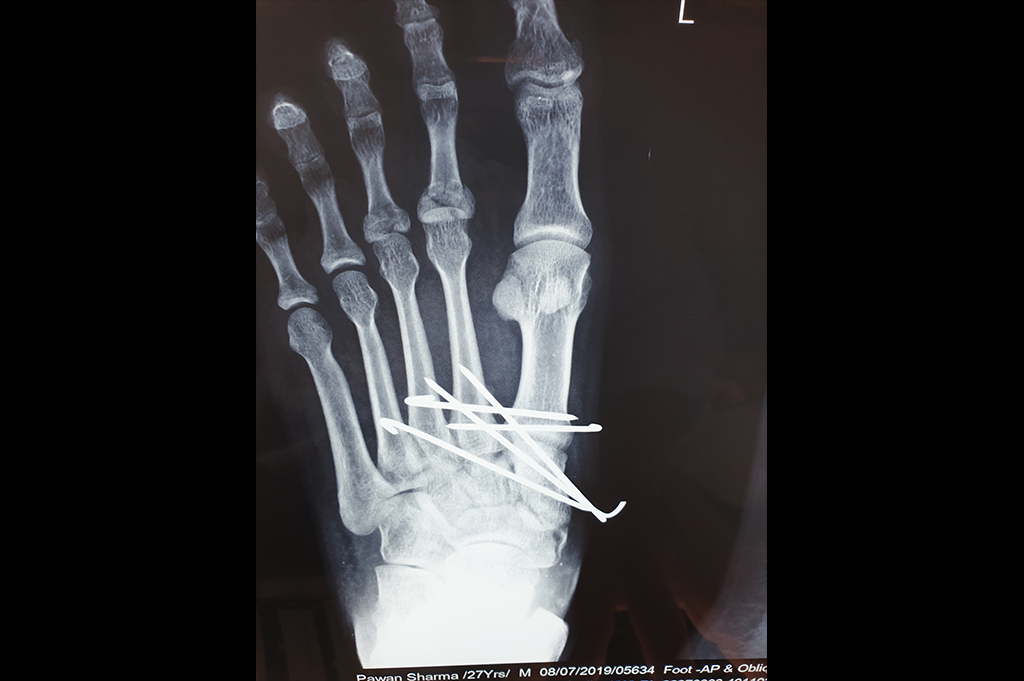

Metarsals with dislocations Lisfranc